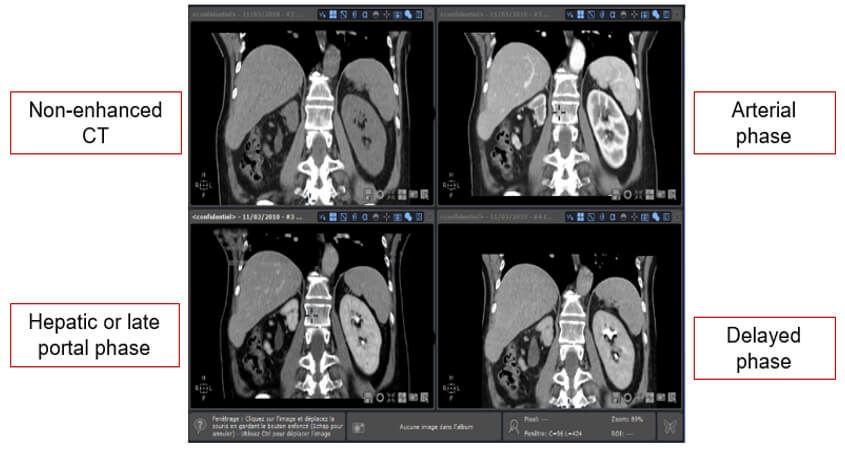

Different Image Phases

Non-enhanced CT helps detect calcifications, fat in tumors, fat-stranding as seen in inflammation like appendicitis, diverticulitis, omental infarction, etc.

The arterial phase is 15-20 sec after bolus tracking. All structures that get their blood supply from the arteries will show optimal enhancement. Hepatic or late portal phase: 50-60 sec after the bolus. Although the hepatic phase is the most accurate term, most people use the term “late portal phase”.

In this phase, the liver parenchyma enhances through the blood supply by the portal vein and you should see already some enhancement of the hepatic veins. The delayed phase is usually 6-10 minutes after the bolus. Sometimes called “washout phase” or “equilibrium phase”. There is wash out of a contrast in all abdominal structures except for fibrotic tissue because fibrotic tissue has a poor late washout and will become relatively dense compared to normal tissue.